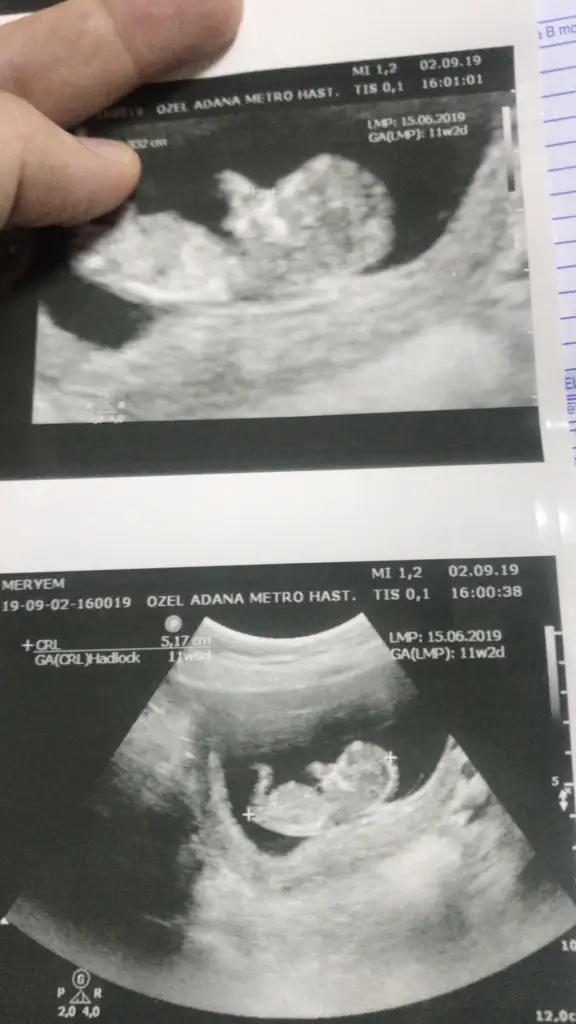

11 haftalık gittiğimde kiz gibi demişti geçen hafta gittiğimde yine kiz dedi sonra kiz değil erkek dedi

Cinsiyet tahmini rica edecektim

usg kafa şekli erkek nubu kız gibi canım.

Kesin diye birsey yok drlar kesin der ben tahminciyim tutabilir tutmayabilir rabbım gönlünüzdekini saglıkla nasip etsin inşallah. 11 yada 12 hafta başka usg varmı